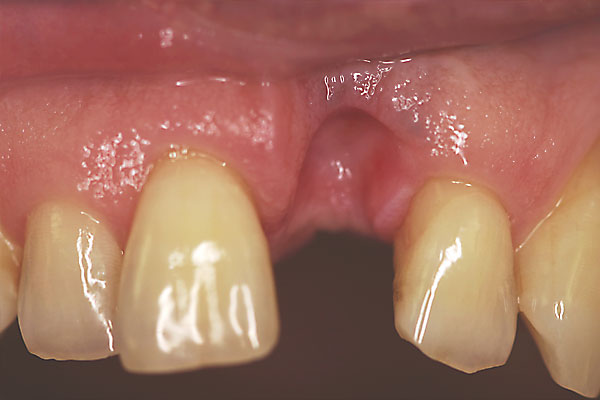

Fall: Einzelzahnlücke nach Zahnextraktion